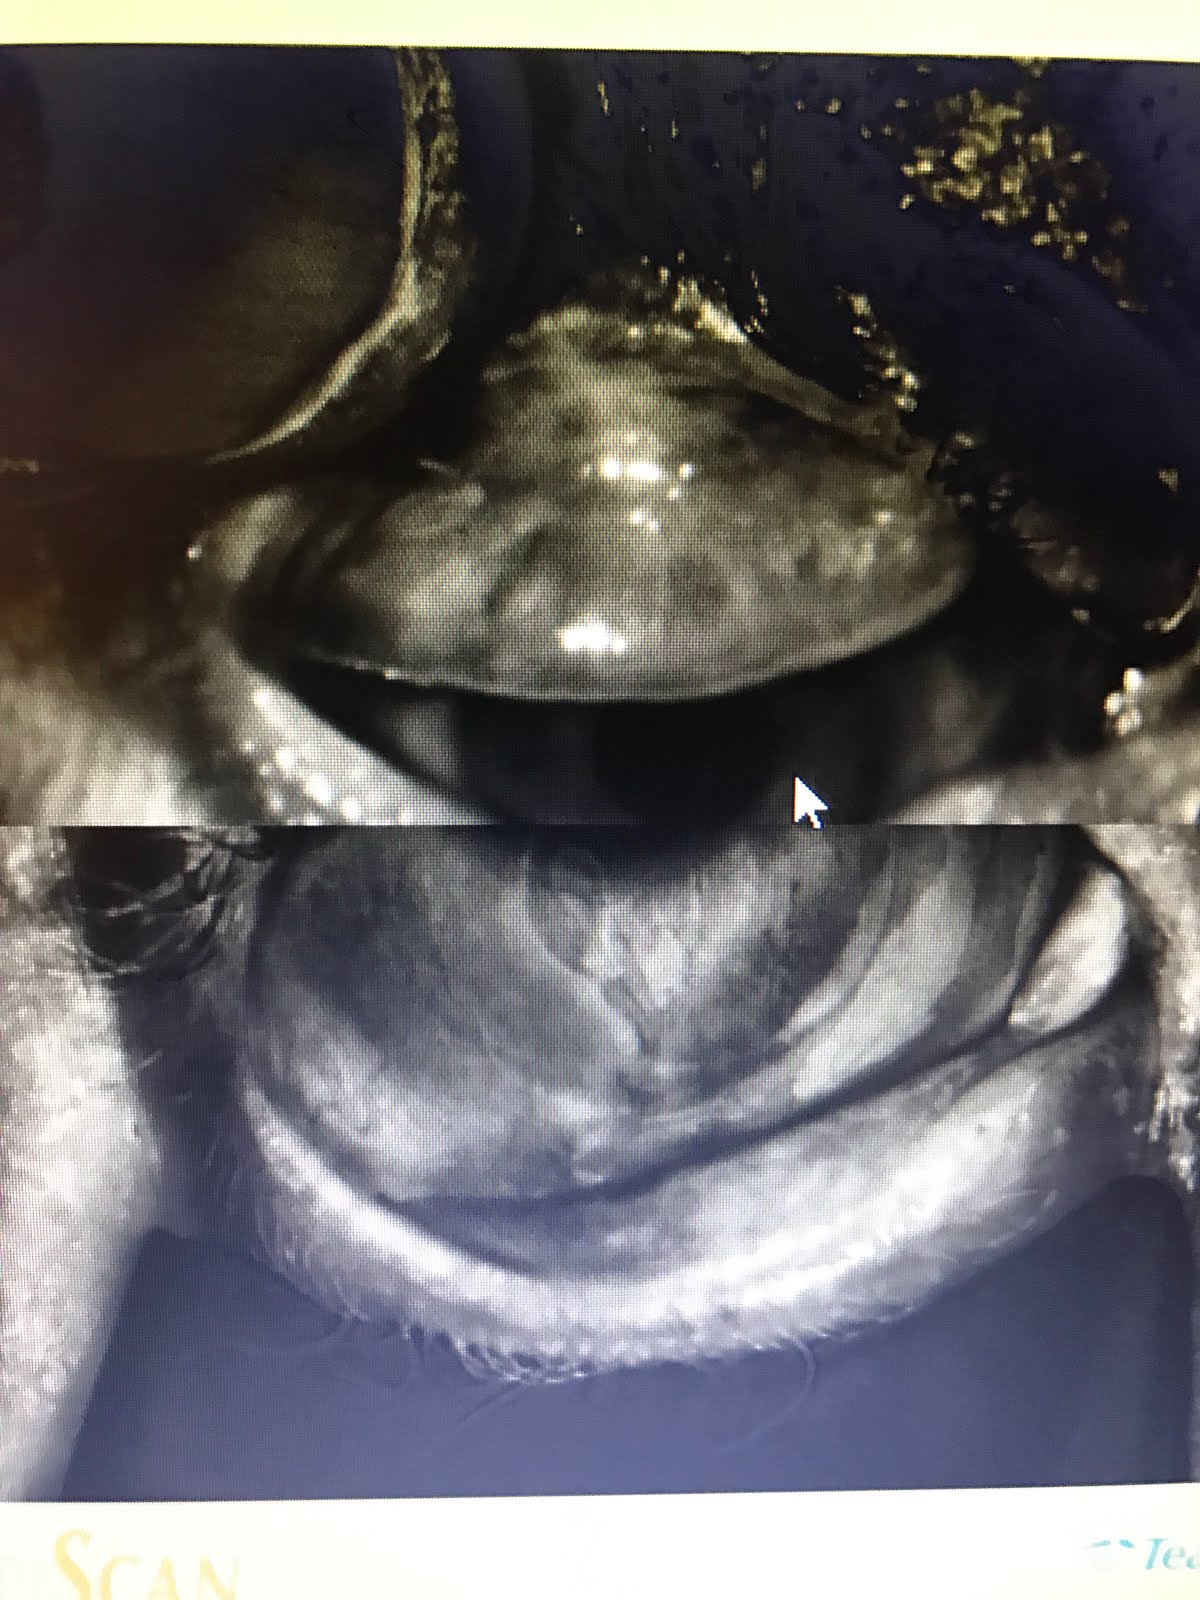

This is his Right Eye (below on left) with upper lids fipped to see Meibomian glands. This is his Left Eye (on the right side of screen). He has very few glands left.

Normal Meibomian Glands should look like “White Piano Keyes Filled with Oil” On Meibography or LipiScan or LipiView Machines seen on bottom left.

Aging, genetics, chronic blepharitis and meibomian gland dysfunction, poor diet, smoking, inflammatory issues and disease, radiation, chemotherapy, previous surgery, and I must add Chronic computer/video game/cell phone use (ie, Computer Vision Syndrome or a new term I will coin called Decreased Blinking Quality Syndrome or Decreased Blinking Rate Syndrome which can happen to even avid readers, skiers, etc) can destroy these precious glands and cause them to never function again. This loss of meibomian glands, decreases the ability of the tears to lubricate the cornea properly, which then leads to the death of the corneal epithelium, thus giving SPK. The death of the corneal epithelium, though is reversible.